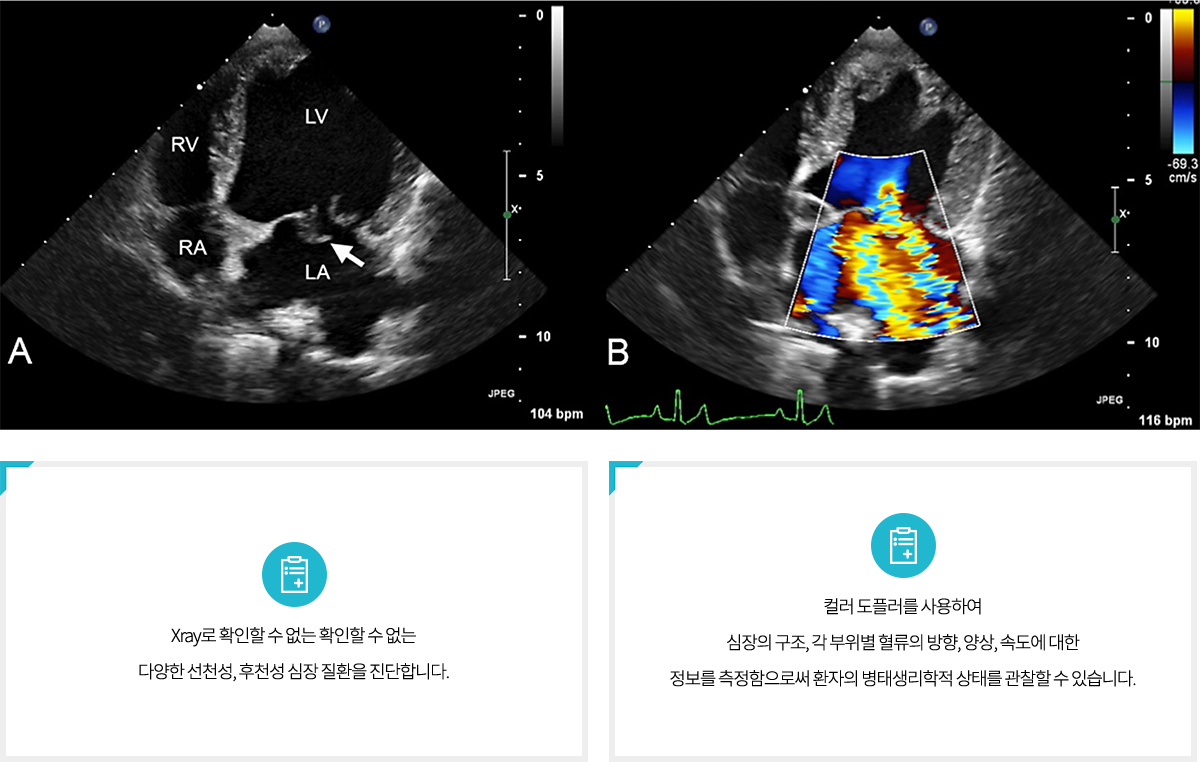

½ÉÀå ÃÊÀ½ÆÄ

ÃÊÀ½ÆÄ °Ë»ç´Â ŽÃËÀÚ·Î ÃÊÀ½ÆÄ¸¦ ½Åü¿¡ º¸³»°í

¹Ý»çµÈ ÆÄ¸¦ ¼ö½ÅÇÏ¿©, ÄÄÇ»ÅÍ·Î À籸¼ºÇØ

³»ºÎ ¿µ»óÀ» ¾ò´Â ¹æ¹ýÀÔ´Ï´Ù.

¿µ»óÀ» ÅëÇØ Àå±âÀÇ Å©±â, ¸ð¾ç, »ö»óÀ» È®ÀÎÇÏ¿©

Áúº´ »óŸ¦ ÆÇ´ÜÇÒ ¼ö ÀÖ½À´Ï´Ù. ºñħ½ÀÀûÀÌ°í ¾ÈÀüÇÏ¸ç °£´ÜÇØ

º¹ºÎ Àå±â °Ë»ç¿¡ À¯¿ëÇϸç, Ä¡·á ÈÄ È¯ÀÚ ¸ð´ÏÅ͸µ¿¡µµ »ç¿ëµË´Ï´Ù.